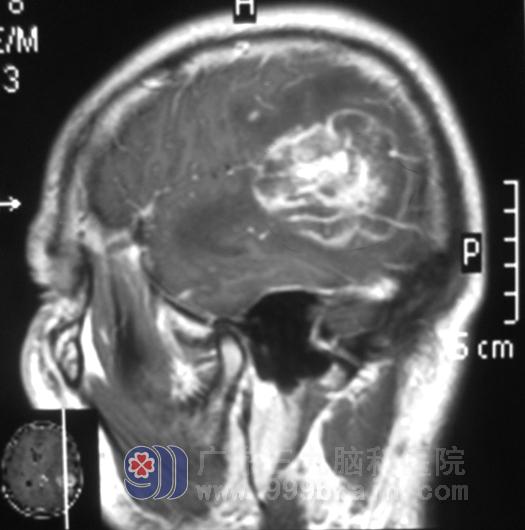

在朋友的建议下,他父亲带着影像检查资料,找到广东三九脑科医院综合神经外科鲁明主任。鲁主任综合几方面考虑有两种可能:一是肿瘤性病变,二是炎性的病变。从我院MRI影像学分析:左侧颞叶占位明确,周围水肿明显,大小为5.5cm×6.1cm×3.1cm,左侧脑室受压变形,患者头痛症状严重并伴恶心,首选手术治疗。

全麻下行“左侧颞叶占位切除+去骨瓣减压术”,病灶基本全切。第二天文哥清醒,回答切题,语言流利。病理报告:(左侧颞顶叶)脑组织呈广泛性坏死、出血,伴胶质细胞增生及慢性炎症反应。术后MRI示病变组织基本全切,水肿较前明显消退;复查MR发现炎性组织以及水肿已基本消失。